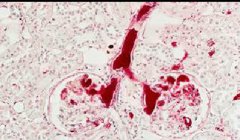

套细胞淋巴瘤(MCL)是罕见的,生物学上和临床上异质的成熟B细胞淋巴瘤,占美国非霍奇金淋巴瘤(NHL)的5%至10%。1,2 有4种形态学变异:小细胞,边缘带状,多形性和胚状体;边缘区样变体MCL的患者经常发生明显的脾肿大。 MCL是男性常见的两倍以上,往往在成 ...